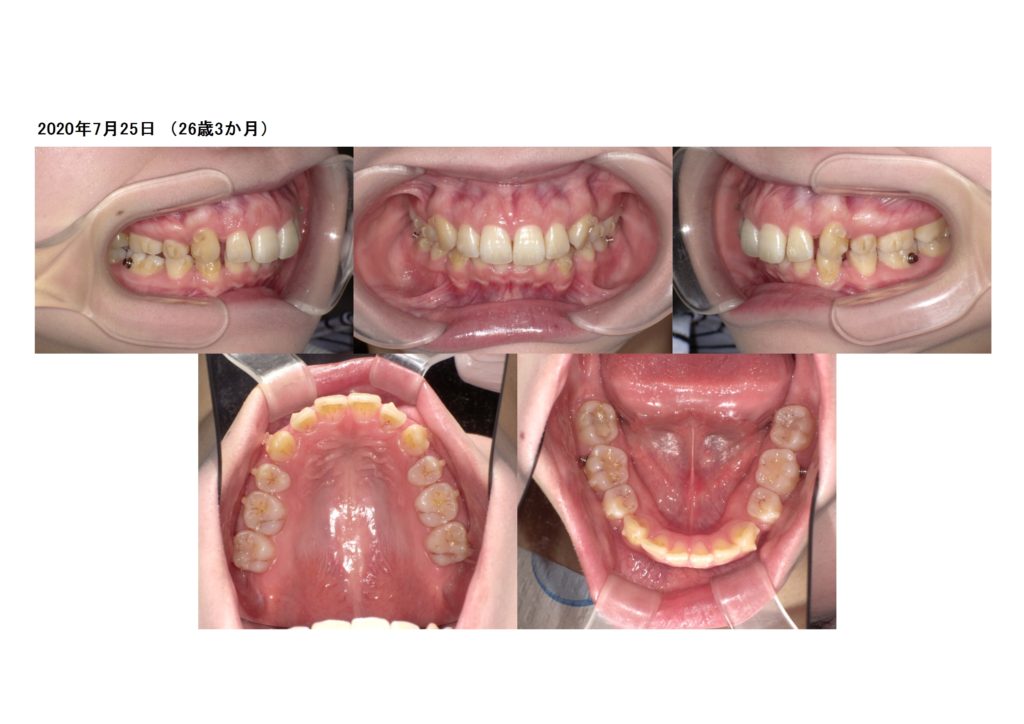

よく見ると、歯の表面にポチっとついているのが分かりますよね☆

これがアタッチメントです。

このアタッチメントは動かし方により、大きさ、部位、形と違ったものがついていきます。